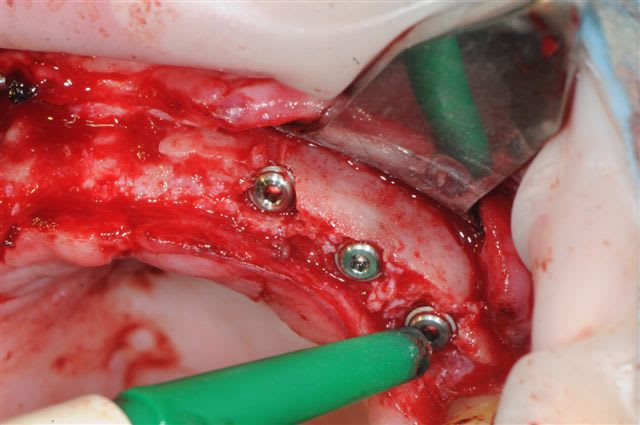

je peux enfin confirmer que la greffe biobank, autorise l'expansion en deuxième intention.

même si je n'ai pas fait un super bombé vestibulaire je me suis permis de faire un mini expansion de crête en particulier sur 22

os magnifiquement vascularisé! excellente adhérence du greffon.

Mais non, mis à part une pénétration profonde (le spreader fait 15 mm pour une prévision d'implant de 10 mm)pas d'autres conséquence que des micros fractures crestale.

l'expansion en 22 à la jonction greffon os propre, faite à l'ostéotome manuel, malgré la non approbation de Thomas, c'est parfaitement passée, et nous avons constatés la parfaite liaison du bloc.